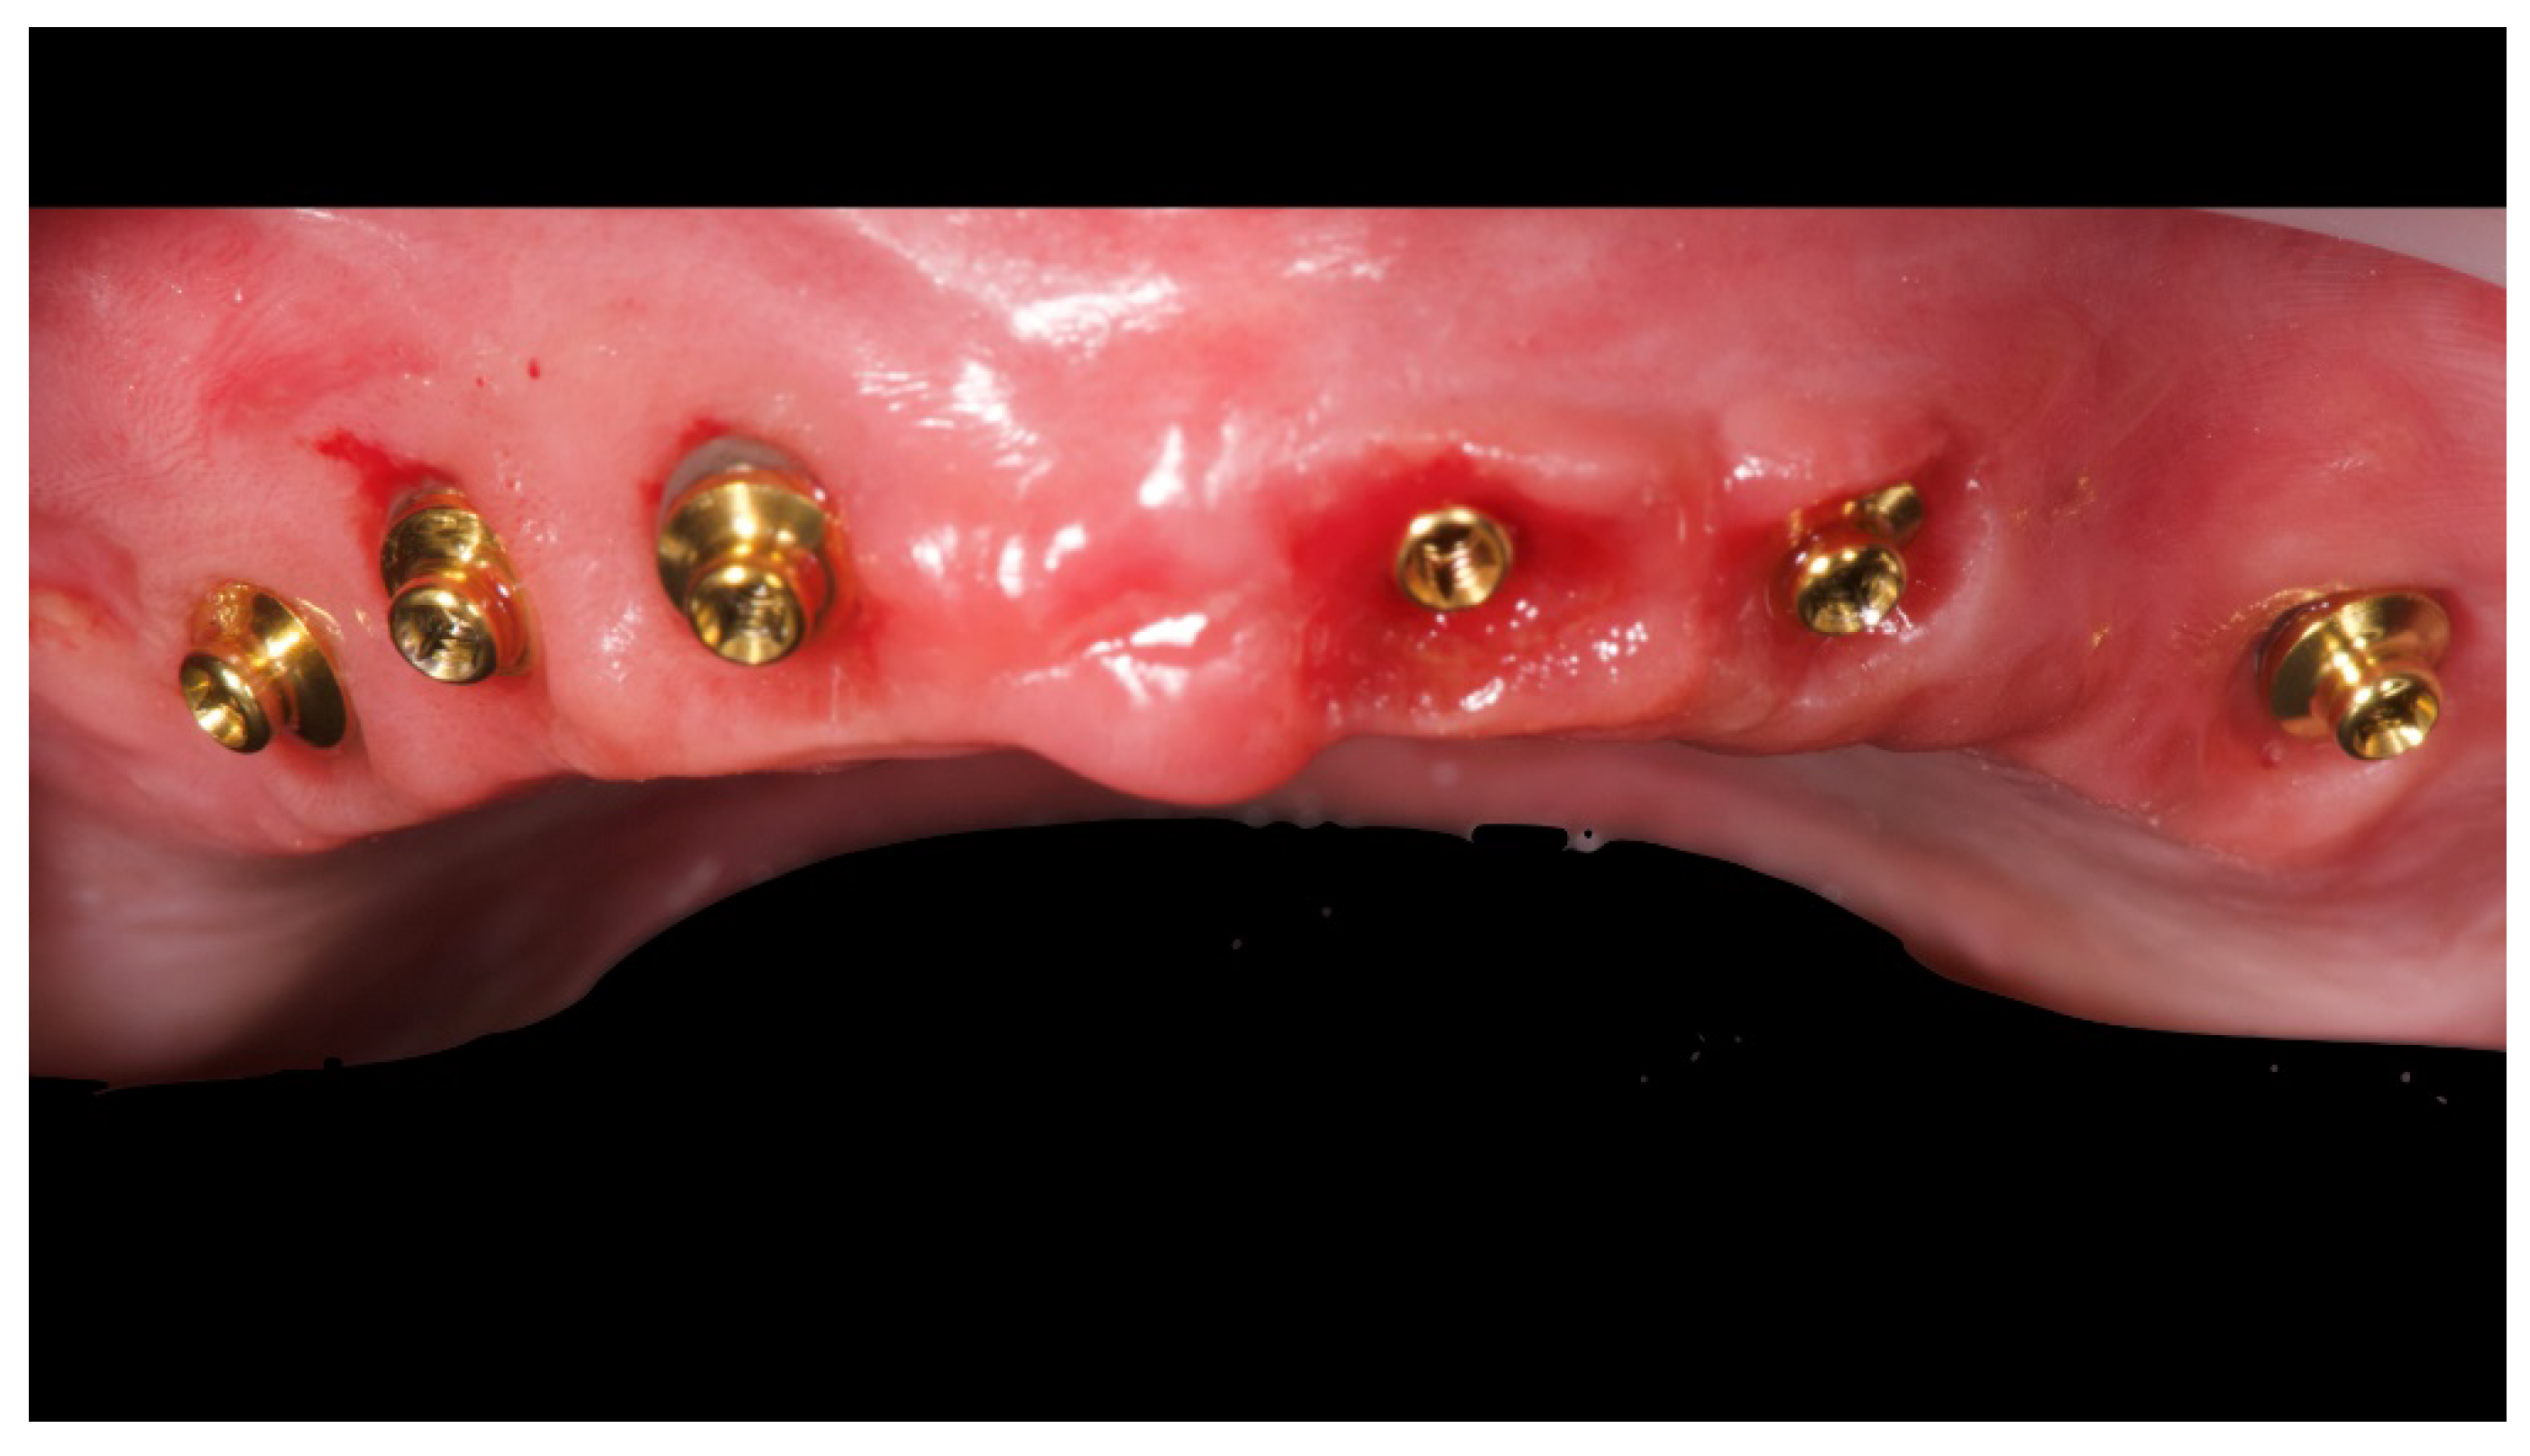

Figure 6.

OT Equator used as abutment for the fixed prosthesis according to the OT Bridge system.